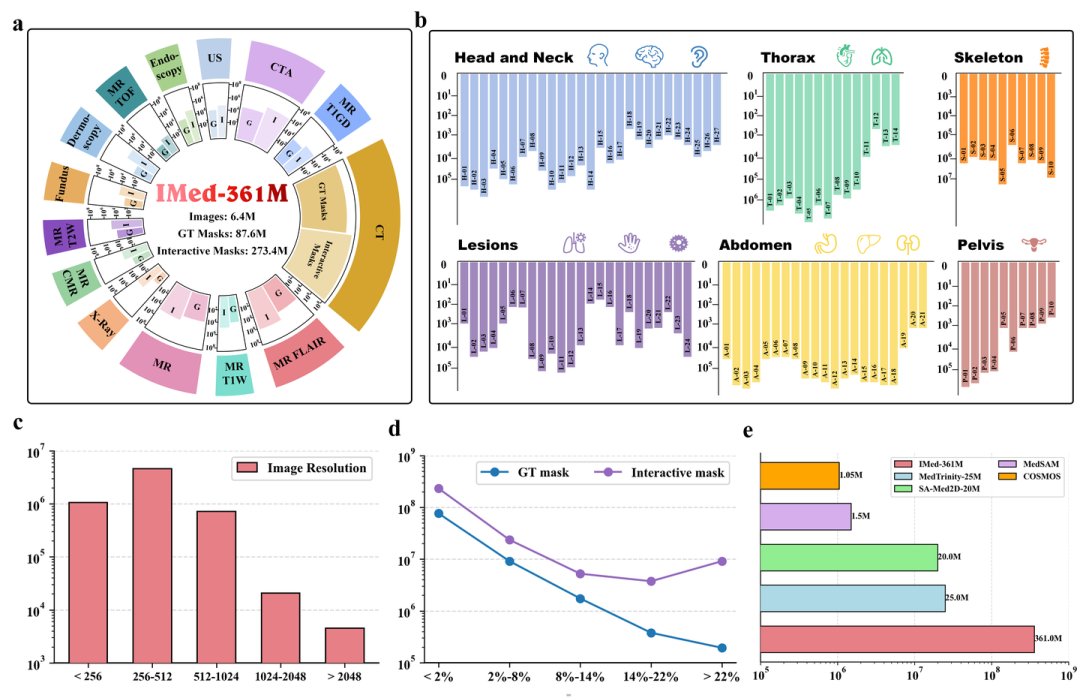

IMIS-Net基线支持多种交互输入(如点击、边界框和文本提示),能够模拟连续交互场景,对分割结果进行动态优化。无论在简单场景还是复杂场景中,IMIS-Net都展现出卓越的性能,为医学图像分割任务提供了更高的灵活性和精度,推动了交互式分割技术的新发展。

图3. IMIS-Net的训练过程模拟了K个连续的交互式分割步骤

本研究提出了IMed-361M,一个专注于交互式医学图像分割的基准数据集。该数据集包含了各种模态的大量医学图像、广泛的分割场景以及密集的掩码,超越了现有仅限于单一任务或简单集成的数据集。利用该数据资源,团队开发了通用的交互式医学图像分割基线模型IMIS-Net,使用户能够通过交互方式(包括点击、边界框、文本提示及其组合)生成符合临床需求的分割结果。与现有基础模型的对比实验结果表明,IMIS-Net在性能上具有显著优势,并在未见过的场景中展现出较强的可迁移性。值得注意的是,IMIS-Net通常需要更少的交互即可达到相当的性能,提高了其在实际应用中的实用性。